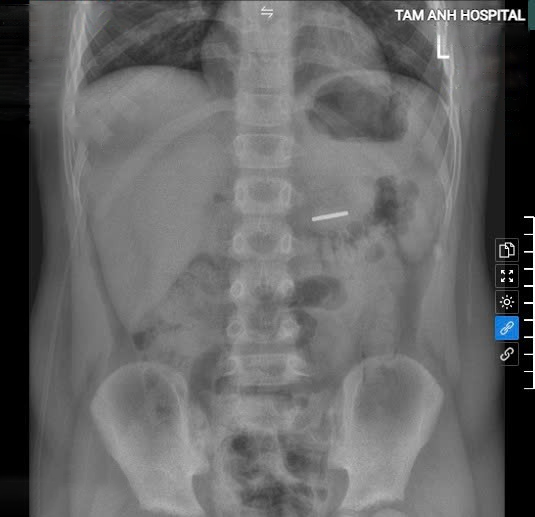

X-ray images confirmed the magnet in the child's stomach. *Photo: Hospital provided* |

Cuong was admitted to the hospital in a conscious state with normal heart and lung function. An X-ray confirmed the presence of a 2.5 cm radiopaque foreign body in his stomach. Doctor Hoang performed an endoscopy and successfully retrieved a dark brown magnet from the D3 duodenum. The boy recovered well and was discharged one day after the intervention.